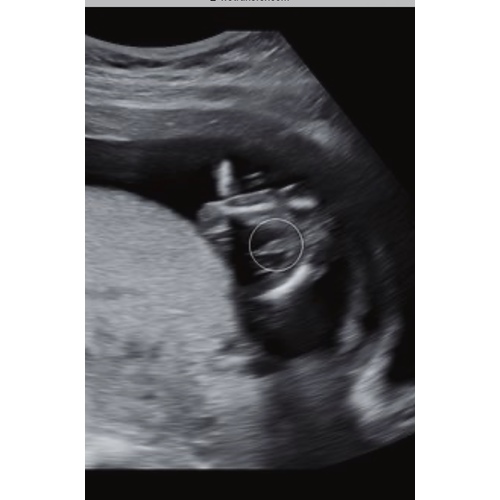

Een jongen

Denk t zelf ook! Maar twijfel zo, geen idee waarom want er zit toch echt wat tussen haha

Ik zie overduidelijk een uitsteeksel zogezegd haha en als je meisje krijg zie je dat niet dan zie je een streepje haha. Wanneer krijg je het te horen?